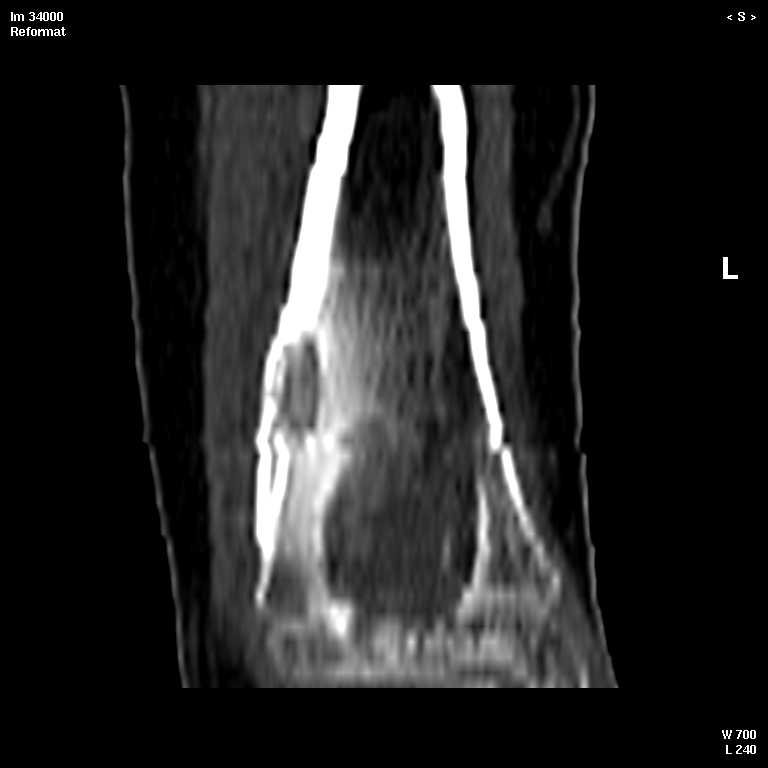

КТ изображения передаю на мой взгляд самые демонстративные. Их любезно записал коллега,

проводивший исследование в другом городе.

Прошу прощения за немного некоректную отправку КТ-снимков но по другому не получается :)